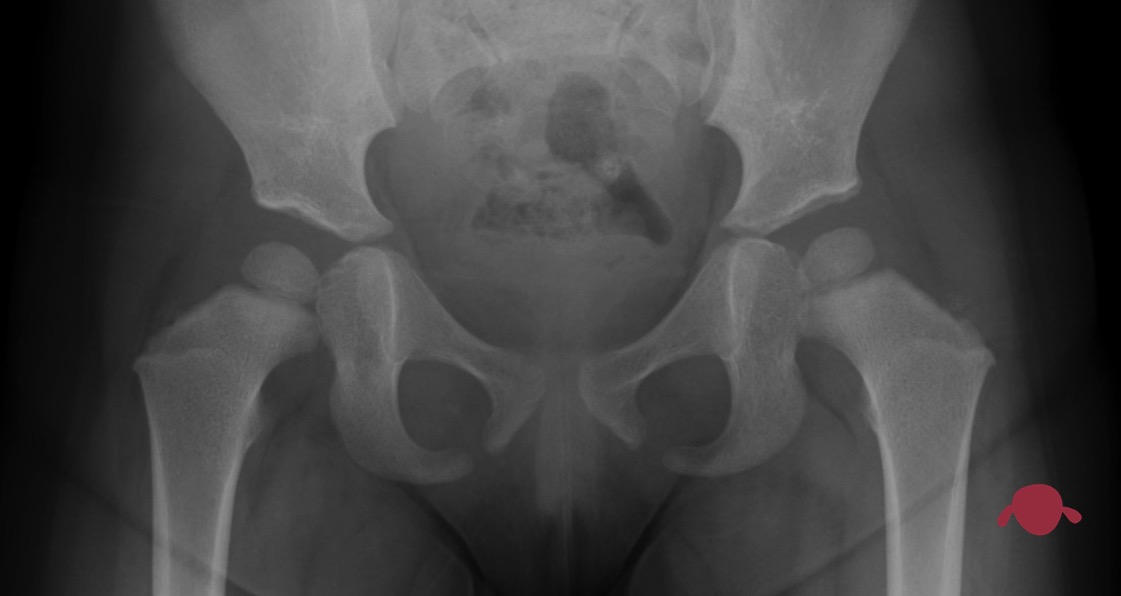

La cadera es la articulación que hay en la ingle y tiene dos partes. Una con forma de bola (la cabeza del fémur) y encima la otra parte, con forma de cuenco o bowl (el acetábulo).

La bola tiene que ser esférica y el cuenco tiene que ser el negativo de la bola para que el engranaje funcione. Así tenemos el primer asunto: la forma. El otro tema es qué parte de la bola esté dentro del cuenco: a esto le llamamos cobertura (qué parte de la cabeza está cubierto por el acetábulo, es decir, contenido dentro del cuenco.

Que el fémur tenga su parte de arriba con forma de bola no es un problema en el recién nacido. Simplemente se forma así. No tenemos que preocuparnos por eso. Sin embargo, el acetábulo no siempre se forma bien cerrado en forma de cuenco o bowl. En ocasiones es más parecido a un plato hondo o incluso en los más graves como un plato llano. Entonces no sujeta bien la bola de la cadera y esta “resbala” fuera del plato. Se queda dentro si el acetábulo tiene forma de un cuenco y se escapa si el cuenco es poco cuenco y más plato llano.

En este caso miramos qué parte de la cabeza del fémur (la bola) está dentro del acetábulo (el cuenco). Como la cadera es una articulación muy móvil, no está tan constreñida (tan sujeta) como otras. Pero si no tiene un mínimo de sujeción dentro del acetábulo podría llegar a salirse. Ese mínimo de cobertura nos gusta que esté en el 50% en la primera prueba que le harán a tu bebé si sospechamos displasia de cadera: una ecografía de cadera (ver entendiendo la ecografía de cadera).